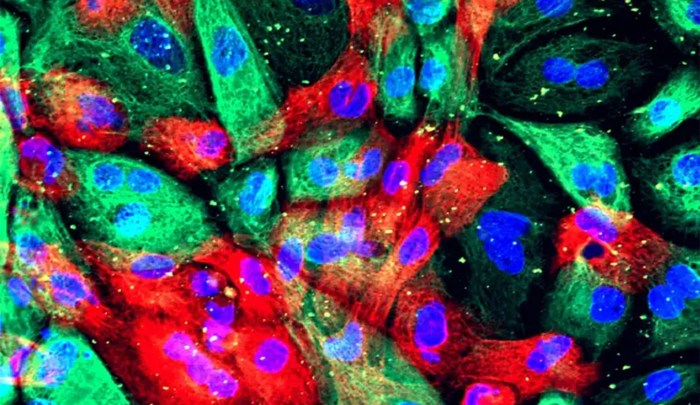

Revelan el papel clave de las modificaciones de ARN en la lucha contra el cáncer de próstata

Un estudio del Centro de Investigación del Cáncer (centro mixto del Consejo Superior de Investigaciones Científicas y la Universidad de Salamanca) revela el importante papel que tiene la enzima METTL1 en la resistencia de los tumores a los tratamientos; por tanto, inhibir esta molécula haría más efectivas las terapias contra el cáncer, entre ellos, el … Continuar leyendo Revelan el papel clave de las modificaciones de ARN en la lucha contra el cáncer de próstata